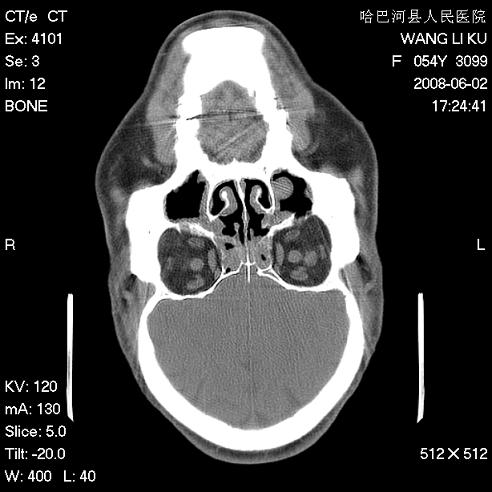

标题: CT13803:反复性鼻塞、流涕一年余 [打印本页]

标题: CT13803:反复性鼻塞、流涕一年余

副鼻窦炎,右上额窦积脓。左眼肌锥内见致密影,视神經受压

1.全组副鼻窦炎2.双侧上颌窦积液

全组副鼻窦炎 肌锥内高密度灶。建议进一步检察检查

1、全组副鼻窦炎。

2、左眼眶肌锥内病变,小血管瘤?建议增强。

1)全副鼻窦炎(左侧上颌窦黏膜下囊肿或息肉)。2)左眼眶肌锥内不规则小结节状软组织密度影;考虑为小血管瘤可能。建议行ct增强扫描检查。

全组副鼻窦炎,左侧肌锥内不规则形软组织肿块影,与眼外肌密度相当,左侧视神经受压,肿块与视神经及眼外肌分界清晰,眼外肌无增粗,眶壁无破坏,球后脂肪间隙不模糊,考虑良性改变,小血管瘤或神经源性肿瘤可能,建议增强扫描。

谢谢,增强扫描做了,眶内病灶与海绵窦同步明显强化,血管瘤